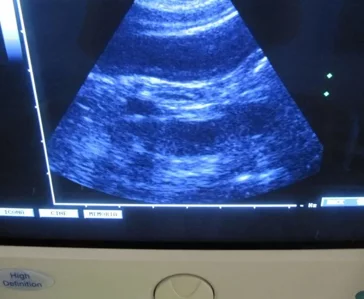

Svolgiamo attività di ecografia internistica e ci rivolgiamo a professionisti esterni nei casi ostici per offrire sempre un servizio di qualità ed avere uno stimolante confronto con i colleghi specialisti. Si eseguono inoltre su richiesta referti radiografici ed ecografici.